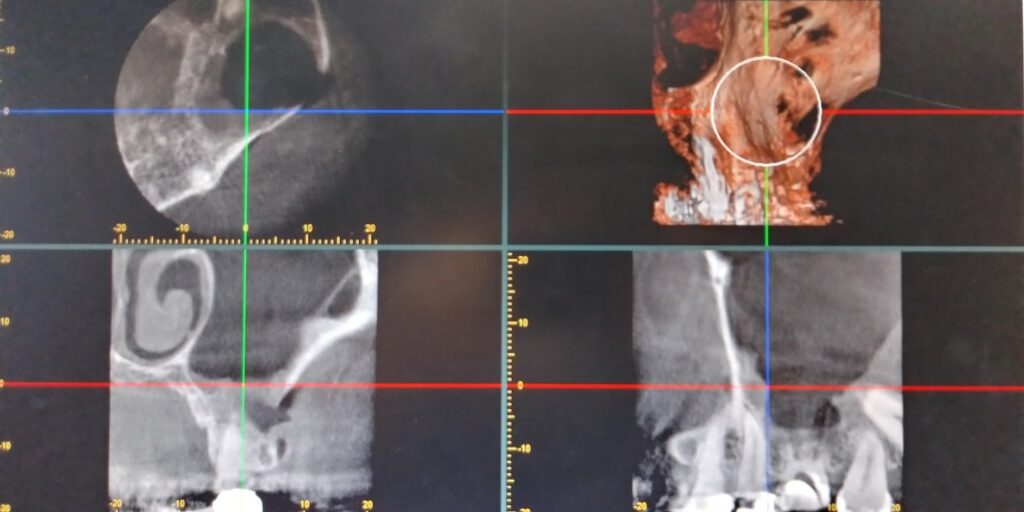

左側上顎洞内にうずら卵大の不透過像をみとめます。左側6は根管充填が実施されています。

左側6の根尖から連続して上顎洞粘膜が挙上されています。上顎洞病変の内部に根管治療材の一部迷入しています。今後残留していると病変に影響を与える可能性も否定できませんでし、病変の増大悪化考えられました。

左側上顎6の歯根は経上顎洞的に頬側根 口蓋根を切除しました。上顎洞内の嚢胞と嚢胞内の歯科材料異物は摘出されています。(術中CT)